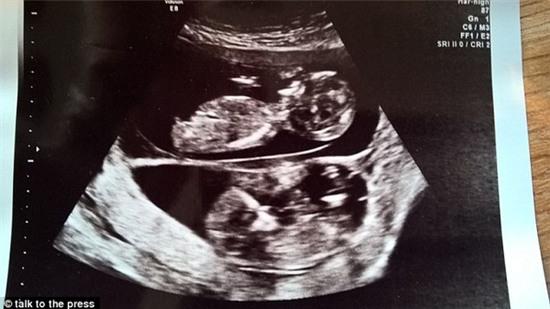

Hình ảnh siêu âm bé Leni và Jenson khi còn trong bụng mẹ.

Bác sĩ siêu âm cho Susie thấy rằng một trong hai cái thai trong bụng cô nhỏ hơn cái còn lại. Vị bác sĩ này cho rằng hai thai nhi này được hình thành từ hai trứng khác nhau và cách nhau khoảng 10 ngày.

“Bác sĩ siêu âm cho tôi nói rằng cô ấy chỉ gặp hiện tượng này một vài lần trong sự nghiệp của mình và đây là một điều vô cùng hiếm. Từ kích thước của hai thai nhi trên hình ảnh siêu âm, cô ấy dự đoán rằng chúng được hình thành cách nhau khoảng 10 ngày. Cả hai chúng tôi chưa từng nghe hiện tượng hiếm hoi này, tôi cũng chưa từng nghĩ là điều này có thể xảy ra”, bà mẹ 32 tuổi cho biết.

Susie nói: “Tôi không thể ngờ mình lại mang thai nhanh như vậy, tôi vừa mới sinh bé Hendrix được 6 tháng. Ngay ở lần đầu siêu âm, các bác sĩ đã nhận thấy được sự khác biệt về kích thước của hai cái thai, nhưng đến lần thứ 2, khoảng 12 tuần sau, họ đã nói rằng hai cái thai cách nhau khoảng 10 ngày”. Hai thai nhi rất khỏe mạnh và phát triển bình thường.